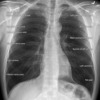

What are bony fragments that can be viewed on a CXR?

* Ribs - start at sternum and trace posteriorly * Sternum - look for continuity * Spine - best view on lateral image * Shoulder girdle - look for displacement * Clavicles - look for symmetry